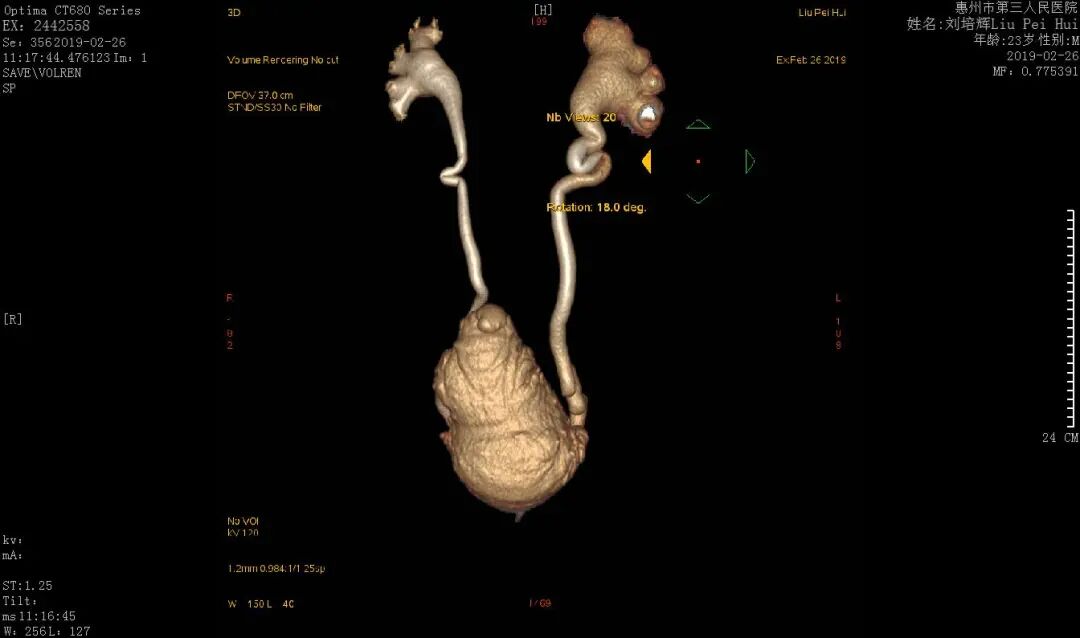

圖示:術(shù)前膀胱輸尿管V級返流,雙腎中重度積水